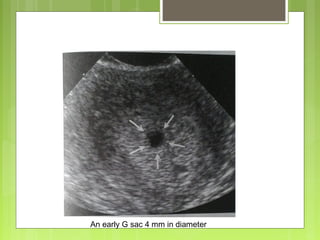

An early G sac 4 mm in diameter

Gestational sac

 Gestational sac – first seen by

 4 weeks+ 1-3 days TVS wen the g sac is 2-3mm

 5 weeks by TAS

 Quantified by calculating Mean sac diameter (MSD) , mean

of three diameters , inner wall margin to inner wall margin in

three planes perpendicular to each other.